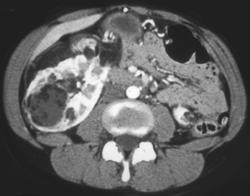

Diagnosis

Normal Renal Arteries